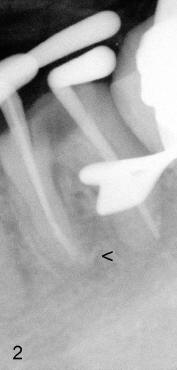

A 31-year-old otherwise healthy Chinese lady has had discomfort since RCT was done for the tooth #19 in home country ~2 years ago (Fig.1). Gutta percha (GP) appears to extrude both in mesial (<) and distal (<<) canals, surrounded by periapical radiolucency (PARL). Two carpules of 2% Lidocaine with 1:100,000 Epinephrine are used for RCT retreat. The patient does not experience any sharp pain during the first injection. Two rubber dams are used due to the short clinical crown of #19 (Fig.2,3). Fig.2 shows master cones (30/.06 M, 40/.06 D) after removal of existing gutta percha using Chloroform. It appears that extruded mesial GP remains outside the apex (< in Fig.2). It is confirmed after removing master cones (< in Fig.3). Working length is controlled by Apex locator during canal re-shaping using GT rotary files. In attempt to remove apparent GP in mesial canal(s) and extruded one outside the apex, #15 hand file is reused at WL+1mm with Chloroform for one or twice for each canal. After adjusting distal GP length, cold lateral condensation is finished with AH26 plus paste and pre-existing PFM crown is recemented (Fig.4). It is apparent that the previously extruded GP is not removed (< in Fig.4).